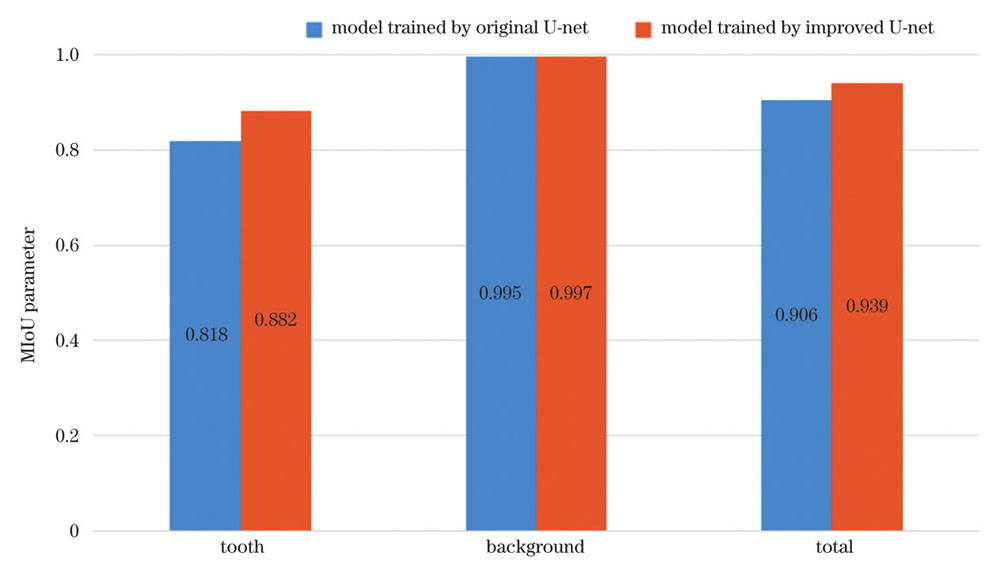

采用常规U-net网络训练的模型和采用本文的改进U-net网络训练的模型的MIoU参数如

MIoU参数可以有效地反映出网络模型对图像的识别精度,其取值为0~1,数值越大表示模型对目标的识别效果越好。对比本文的改进U-net网络和常规的U-net网络训练的模型的MIoU参数,可以看出改进后的算法对牙齿的识别效果提高了0.064,对背景的识别效果也提高了0.002,整体提高了0.033。通过对MIoU参数的定量分析可知改进后的算法有更好的识别能力。